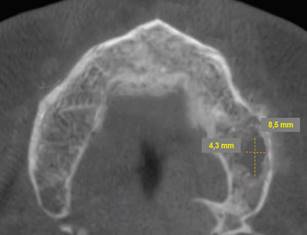

Se solicitó inicialmente radiografías periapicales de la zona afectada, donde se evidenció perdida de la continuidad del trabeculado óseo con zonas osteolítica irregulares, tenues y sin presencia de restos radiculares o cuerpos extraños (Fig.4 A, B). Para evaluar extensión de la lesión, se solicitó CBCT de maxilar, en el cual se observó un área radiolúcida y osteolítica localizada a nivel del tejido óseo maxilar, de 8,5 mm x 5,4 mm, de bordes irregulares, poco definidos, que no comprometían corticales vestibular, palatina, ni seno maxilar (Fig. 5). El estudio microscópico de los restos de tejido necrótico confirmó áreas de necrosis del tejido óseo con infiltrado inflamatorio, confirmando diagnóstico de ONM.